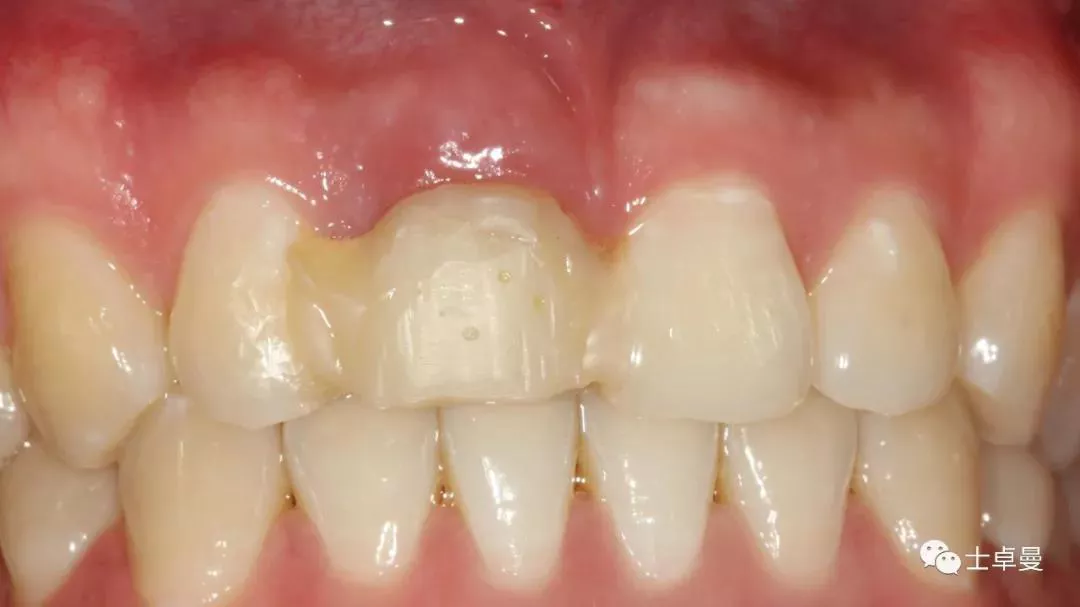

临时修复后2个月,龈缘及龈乳头位置理想,软组织健康

· 2个月后,见唇侧骨弓轮廓可,龈缘及龈乳头形态自然,去11临时修复体,植体ISQ值测定82,个性化取模,试戴Variobase氧化锆基台+LAVA氧化锆单冠,就位被动性良好,增加基台扭力至35Ncm,粘接固位上部冠,调合抛光。

完成永久修复,骨弓轮廓、龈缘及龈乳头形态自然,可见牙龈点彩,修复体外形及色泽可,患者满意。